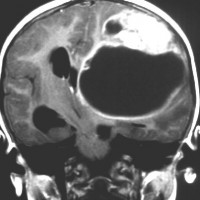

2歳の子どもの例

2歳の時に右の片麻痺と意識障害で発症しました。手術できれいにとれて,20年経ちますが再発はありませんし,運動麻痺もありません。この画像を見ると左の一次運動野が侵されていて,麻痺が治るということは信じられないのですが,2歳以下の小さな子どもの麻痺は治ることがあります。乳幼児のこの腫瘍は積極的な摘出を行った方がいいでしょう。

- 頭頂葉と前頭葉表面に広がり数センチを越える巨大なのう胞性腫瘍となります

- 大脳深部方向へ食い込むのう胞があり,固形腫瘍部分は結節様に表在することが多いです